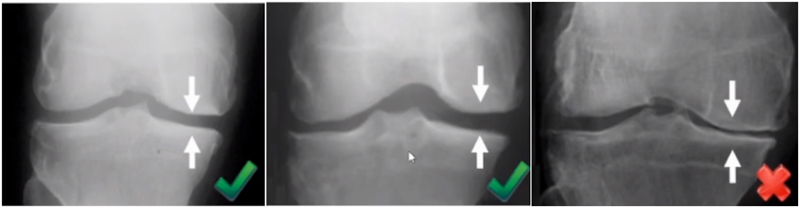

牛津单髁影像学判断的标准为通过负重正位片来判断内侧间室关节软骨的磨损程度。内侧间室关节间隙变窄,股骨内侧髁与内侧胫骨平台成“骨磨骨”状态,说明内侧间室软骨磨损丢失。如果没有在正位片观察到“骨磨骨”,则需要通过内翻应力位片或rosenberg位检查,找到骨磨骨的证据。如果以上均没有显示骨磨骨,需考虑关节镜检查,只有在达到“骨磨骨”的情况下才考虑行UKA。

检查时注意X线的投照角度要平行于关节线方向,以保证准确。

可以矫正畸形,恢复关节间隙和MCL张力

AMOA的X线正位的表现